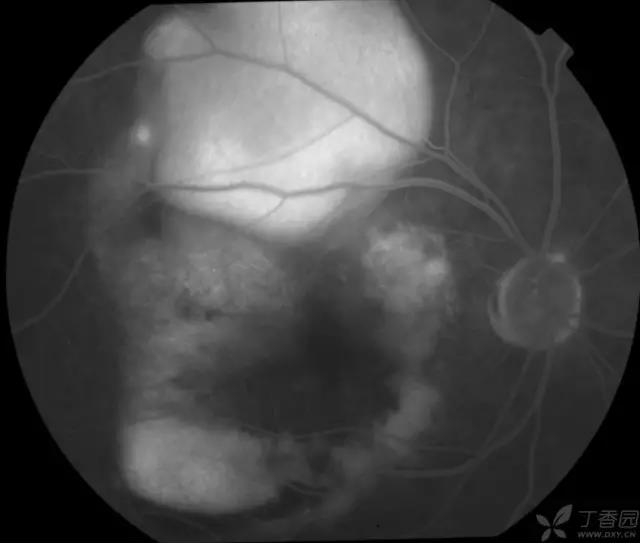

▼颞上分支静脉阻塞

实用贴:眼科病例高清图片